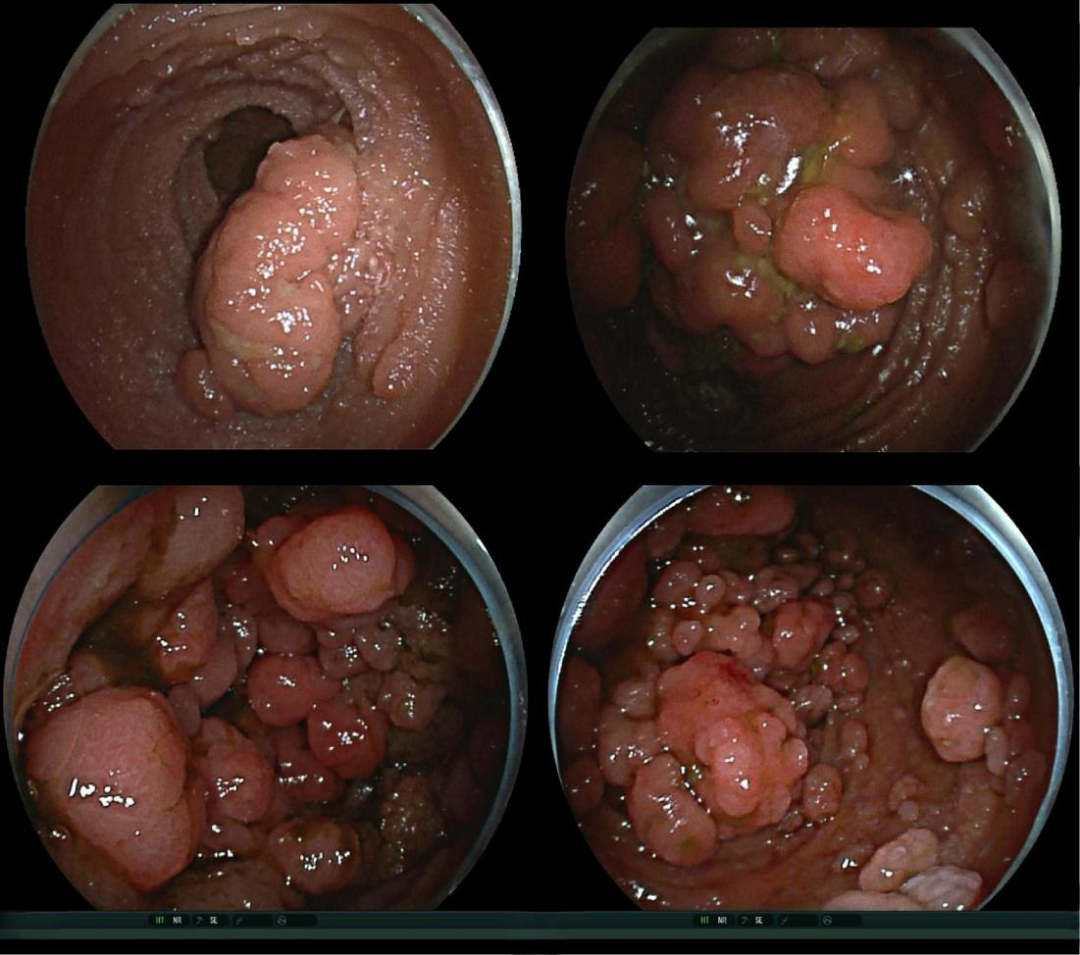

内镜检查  入院后患者完善经肛、经口小肠镜检查(图2):经肛进镜至距回盲瓣150cm处,肠腔明显扩张以致外套管跟进困难,小肠及全结肠可见密集分布近百枚山田/型息肉,大小1.0~3.0 cm,经口小肠镜进镜至距幽门150 cm处,所见十二指肠、空肠黏膜密集分布百余枚0.5~4.0 cm息肉,其中以十二指肠及空肠近端为主,部分堵塞肠腔,术中切除大于3 cm息肉30余枚。

图2:回肠远端、空肠上段及十二指肠多发息肉,大小0.5~4.0 cm,肠腔扩张。